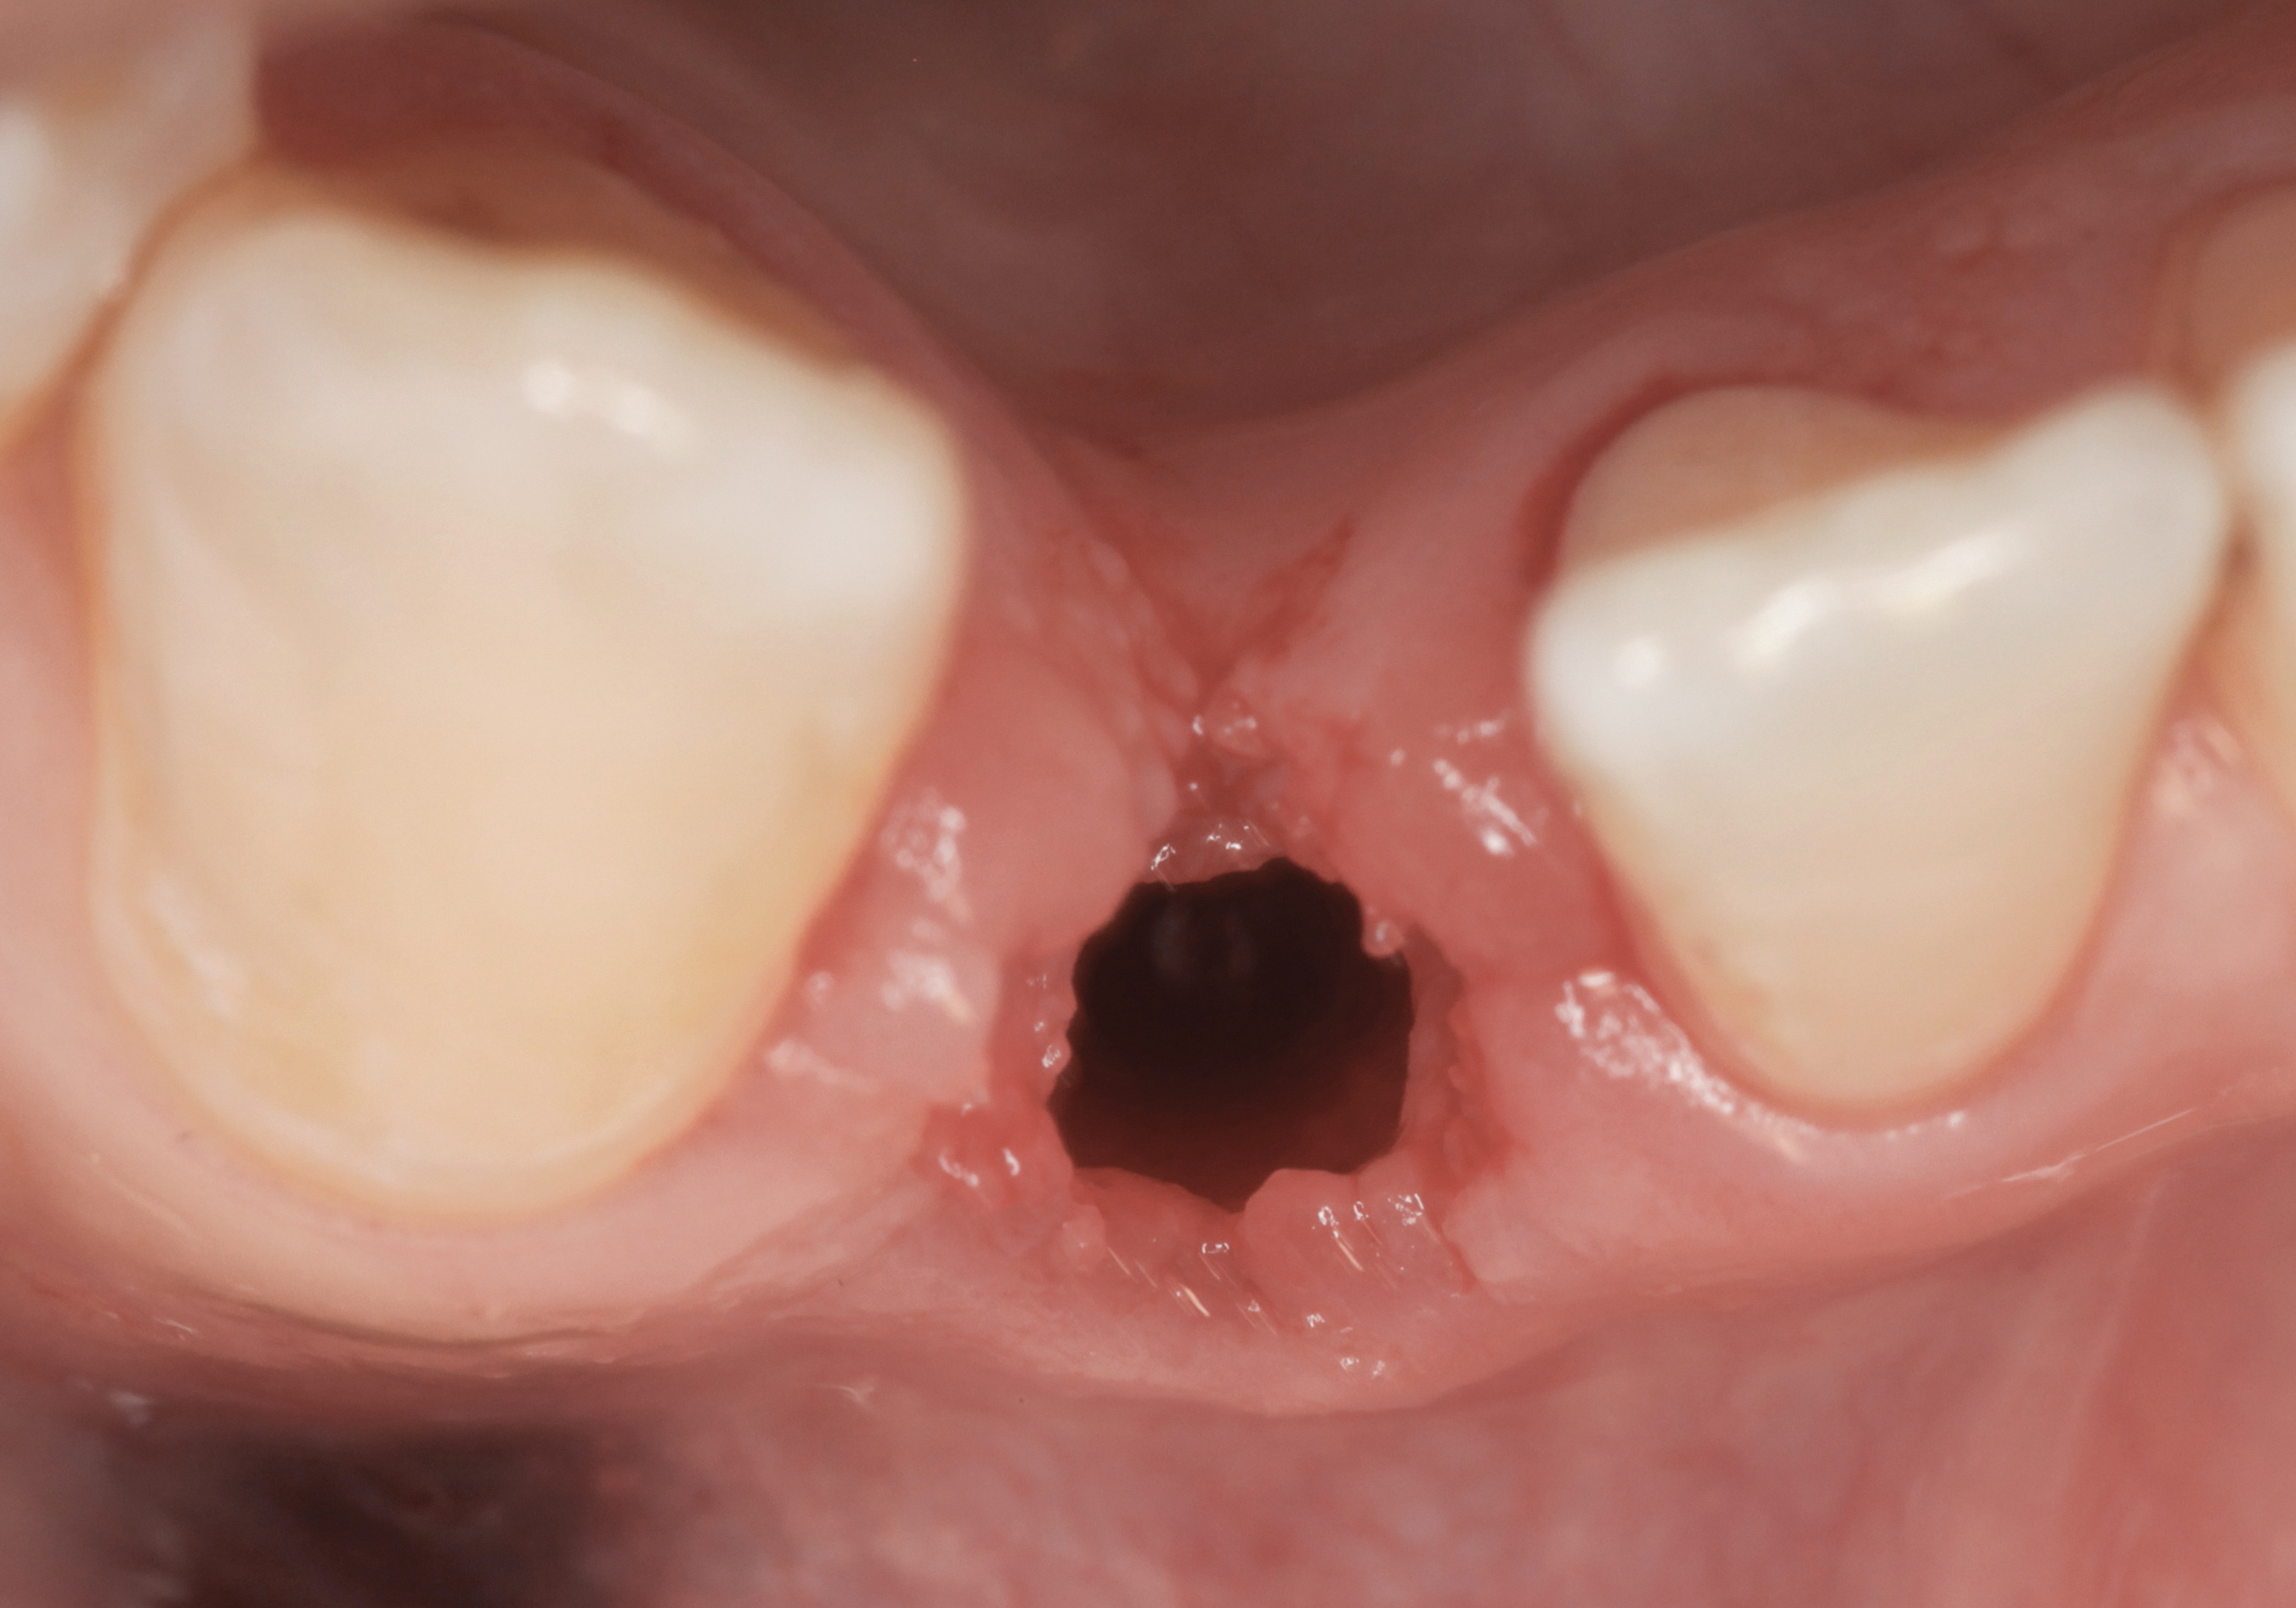

Fig 33. Excessive facial angulation of the implant placement shown with an abutment driver in the access screw hole.

Figure 33

Fig 34. A surgical cover screw was placed in an attempt to decoronate the implant and gain soft-tissue coverage in situ.

Figure 34

The following case report provides an example of this case scenario: A 24-year-old white male presented with congenitally missing tooth No. 26 restored with a single-tooth cement-retained implant restoration. The implant was placed excessively to the facial aspect of the edentulous site and too shallow, and the periodontal phenotype was thin scalloped (Figure 32). In an effort to mimic the lost midfacial soft tissues, pink ceramics were used as a cosmetic facade. Even though the restoration was not in the esthetic zone, the patient was highly displeased with the esthetic outcome and sought remediation.

The crown and screw-retained custom abutment were removed, and a surgical cover screw was placed into the implant, thereby allowing spontaneous gingival augmentation in situ (Figure 33 and Figure 34). Note that the lingual aspect of the implant site was significantly more coronal than the labial aspect, which was positive because the defect would be limited to a facial–lingual defect. A fixed RBR bridge was cemented on the adjacent teeth and used as a tooth-supported transitional provisional restoration (Figure 35). A few weeks were allotted to let the soft tissue heal and migrate around the cover screw (Figure 36) to see if there would be complete coverage, thereby allowing a soft-tissue augmentation procedure to be performed with primary flap closure as in clinical scenario No. 2. The major obstacle in achieving a positive tissue response was that the implant depth was also deficient because the implant–abutment connection was at the level of the free gingival margin. It was decided that the best treatment option would be to remove the implant. A high-powered reverse-torque device (Fixture Remover Kit, NeoBiotech, www.neobiotechus.com) was used to remove the implant atraumatically (Figure 38 through Figure 41). The implant socket was allowed to heal for several months not unlike an extracted tooth (Figure 42). A new implant was placed in a better position from both a restorative and esthetic perspective (Figure 43), and after a few months of healing, a new crown was made (Figure 44). A satisfactory functional and esthetic result was achieved (Figure 45 and Figure 46) without employing pink porcelain.